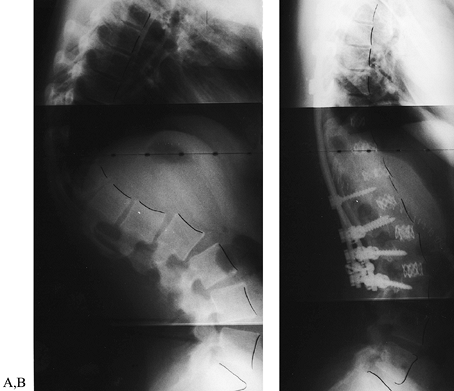

![]() |

|

Figure 161.16. A: Postlaminectomy sagittal thoracolumbar kyphosis from resection of an arteriovenous malformation. B:

Postoperative radiograph with intervertebral Harm’s cages used as structural intervertebral grafts and posterior segmental instrumentation [three-stage (posterior–anterior–posterior), same-day surgery]. (Images courtesy of Dr. Harry Schufflebarger, Miami, FL.) |